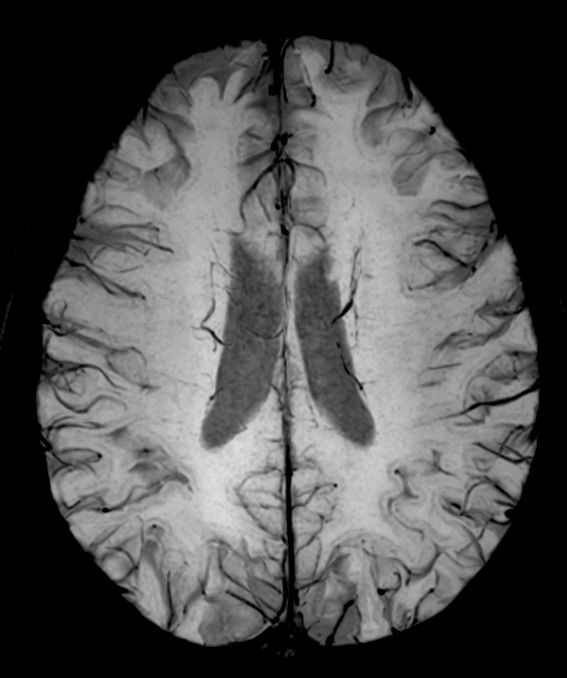

T2w TSE MultiVane XD

-